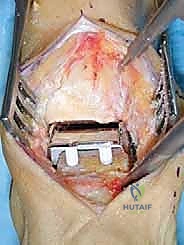

1. الشق الجراحي والوصول للمفصل

يقوم الجراح بإجراء شق أمامي طولي (Anterior Approach) في منتصف الكاحل. يتم إبعاد الأوتار والأوعية الدموية والأعصاب بعناية فائقة (هنا تتجلى أهمية مهارات الجراحة الدقيقة التي يمتلكها الدكتور هطيف) للوصول إلى محفظة المفصل.

2. إزالة الزوائد العظمية وتحرير المفصل

يتم إزالة النتوءات العظمية (Osteophytes) التي تسبب الألم وتحد من الحركة، وتحرير الأنسجة المتليفة لاستعادة المرونة الأولية للمفصل.